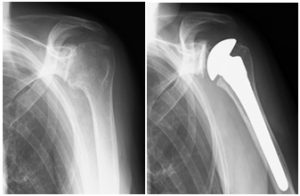

人工肩関節置換術

リウマチ肩による痛みと可動域制限があり、人工肩関節置換術を施行しました。痛みは消失し、肩関節可動域も改善しました。